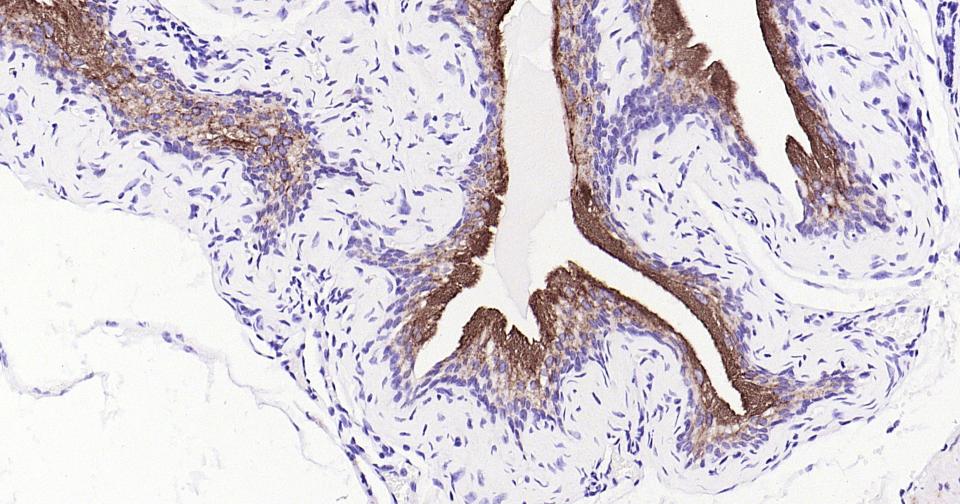

Paraformaldehyde-fixed, paraffin embedded Human Bladder; Antigen retrieval by boiling in sodium citrate buffer (pH6.0) for 15 min; Antibody incubation with UPK3A Monoclonal Antibody, Unconjugated(bsm-61004R) at 1:400 overnight at 4°C, followed by conjugation to the bs-0295G-HRP and DAB (C-0010) staining.